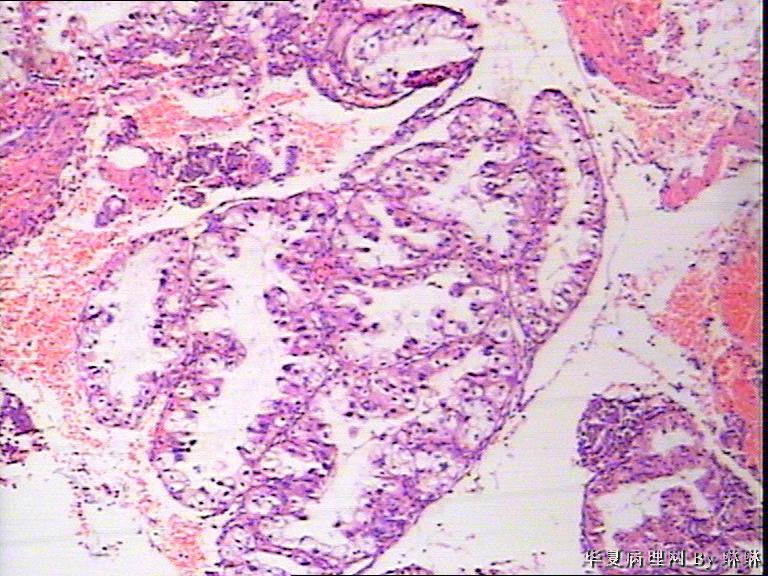

患者女性,38岁,月经量多4个月,曾服用止血药物,无其他病史。

• 子宫内膜,请教图3

图3

腺体呈高度分泌反应,我们必须结合病史,考虑是否药源性反应,或持续黄体期子宫内膜.

开始临床没有提供怀孕的病史,后来我们有咨询临床科室,大夫还是说没有用药、月经正常,刚过了经期,月经量多,这次月经持续时间长入院。所以我们开始排除了高度分泌的A-S反应,看到腺体增生呈乳头状,还有异型性,而且镜下部分子宫内膜还有增生期改变的,不完全是高度分泌的。再三考虑后还是要求临床查了血HCG,结果显示HCG370多。最后我们发了单纯性增生伴高度分泌。

复杂性增生伴分泌反应